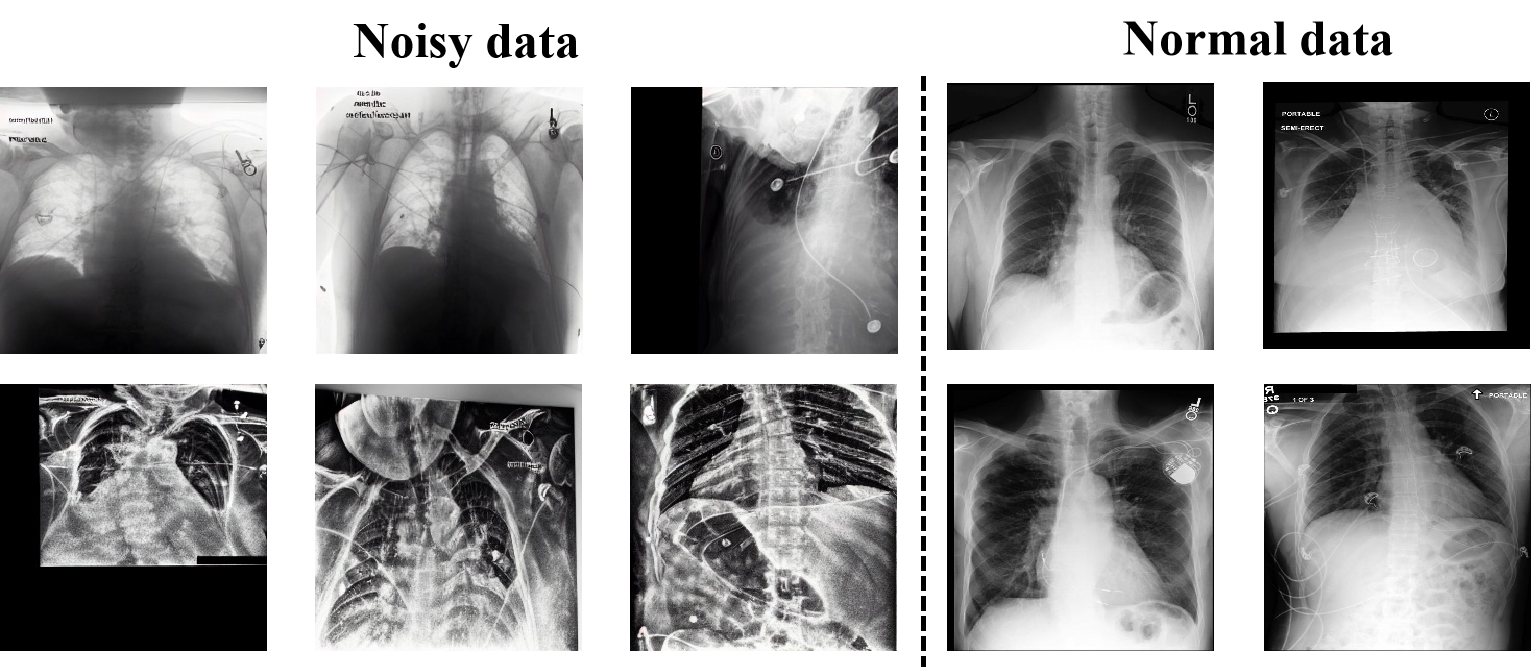

As illustrated in Fig. 6, we visualize multiple noisy images filtered by LNFS and provide several normal images as a reference. We can observe that these abnormal samples exhibit notable deviations from normal images, featuring low signal-to-noise ratio and shape distortion, et al. These deviations also result in the lack of the alignment with their respective medical reports.

To demonstrate the superiority of our coarse-to-fine anomaly detection method, we compare the filtered samples generated by manifold modeling and explicit supervision phases using TSNE. As shown in Fig 7, several noisy points near the decision boundary or nearby normal points, are misclassified as normal data during the manifold modeling stage. However, explicit supervision successfully identifies such noisy points and corrects the mistakes. Finally, 2000 images are identified as noisy data and excluded from training.